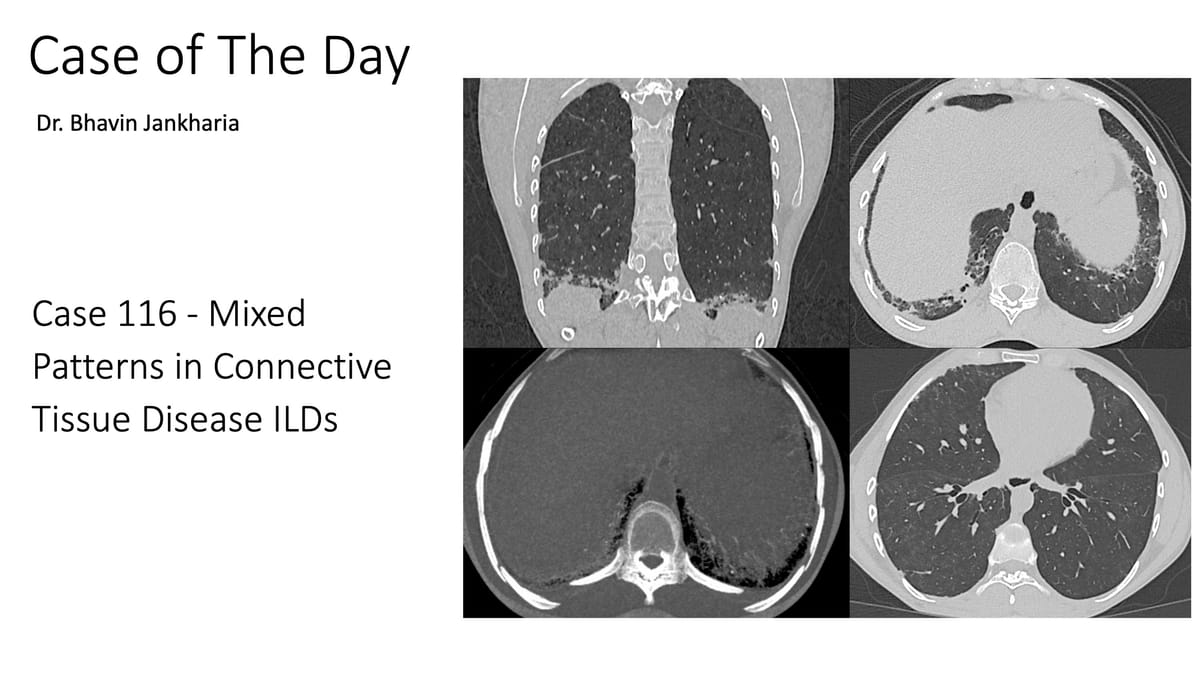

Mixed NSIP/OP patterns typically point towards the likelihood of connective tissue disease and should be mentioned in the report

Mixed patterns are increasingly being recognized in CTD ILDs and should be mentioned in the report.

This complements the earlier post on Connective Tissue Disease ILD Patterns, where I did not discuss "mixed patterns" in detail and the previous post titled "Mixed Patterns in Connective Tissue Disease ILDs" as well as last month's post titled "Decoding DPO and CiOP"